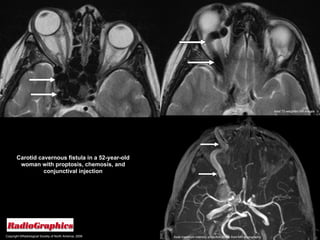

Carotid Cavernous Fistulas  Often manifest with the  classic triad  of pulsatile exophthalmos, conjunctival chemosis, and an auscultatory bruit.  A CCF may result from trauma or surgery, or it may occur spontaneously.  Spontaneous CCF have been reported in patients with  osteogenesis imperfecta ,  Ehlers-Danlos syndrome , and  pseudoxanthoma elasticum .

Carotid Cavernous Fistulas  CT and MR imaging; Proptosis. Engorgement of the superior ophthalmic vein. Enlargement of the ipsilateral extraocular muscles.  May be evidence of venous thrombosis in the lumen of the superior ophthalmic vein or cavernous sinus.

Copyright ©Radiological Society of North America, 2008 Carotid cavernous fistula in a 52-year-old woman with proptosis, chemosis, and conjunctival injection Axial T2-weighted MR images Axial maximum intensity projection image from MR angiography